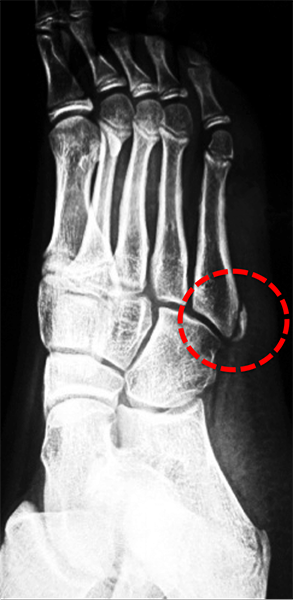

4. Osteocondrose da Base do 5º Metatarso ( Doença de Iselin ):

É a osteocondrose que acomete a base do quinto metatarso e relaciona-se diretamente com a inserção do tendão fibular curto nesta região. Foi descrita por Iselin em 1912.

É uma lesão pouco comum que acomete tanto em meninos quanto em meninas, mas principalmente em jovens esportistas entre 7 e 10 anos.

O paciente queixa-se de dor e inchaço localizado na lateral do pé.

A palpação do local é dolorosa e piora com o movimento forçado de flexão plantar e inversão (movimento do pé para baixo e para dentro).

Ao raio X pode-se observar alargamento da base do 5º metatarso e irregularidade no padrão de ossificação da fise (cartilagem de crescimento).

O tratamento é conservador e consiste em evitar atividades de impacto, uso de medicação analgésica, gelo e, ocasionalmente, imobilização temporária do pé e tornozelo.

A fisioterapia e o retorno gradual à atividade esportiva são liberados após a melhora dos sintomas, que ocorre entre 6 e 12 semanas após o início do tratamento.

A cartilagem de crescimento ou fise da base do 5º metatarso ossifica-se completamente por volta dos 12 e 14 anos de idade.